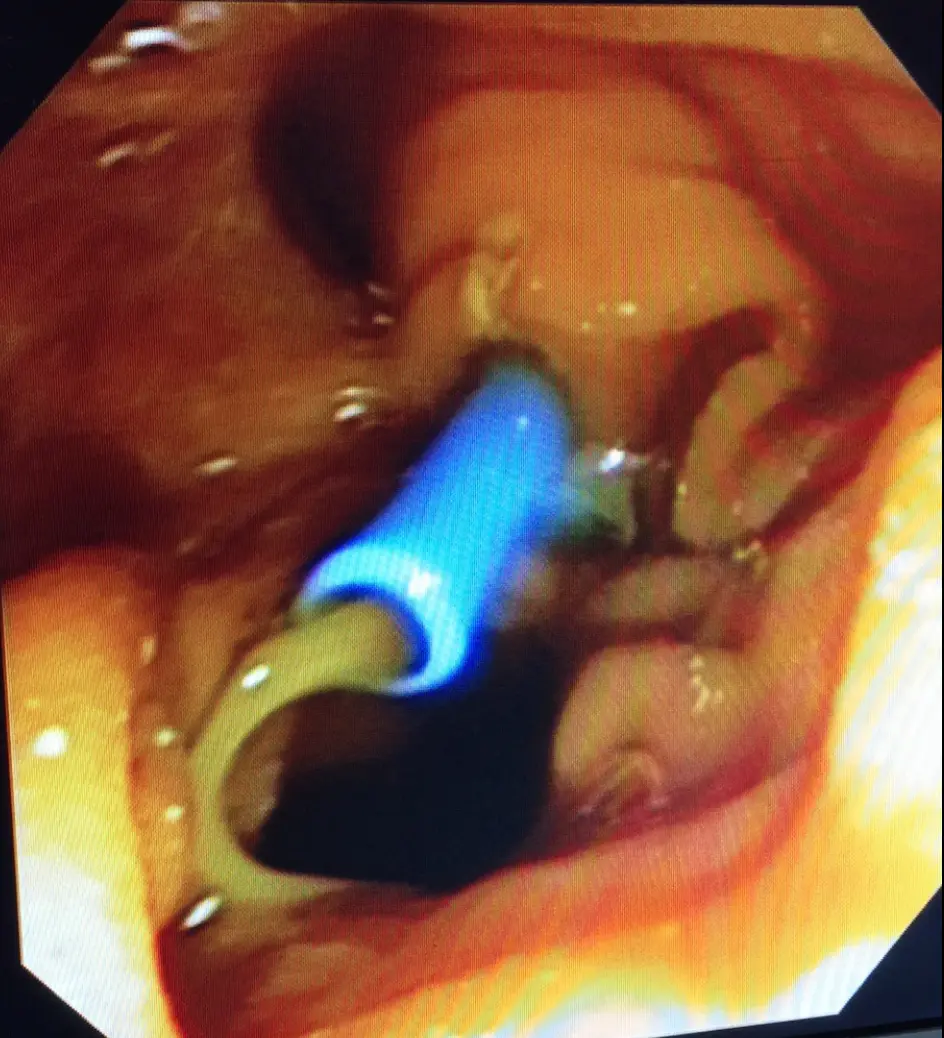

Colangioresonancia: este estudio permite evaluar la presencia de Cálculos en las vías biliares, esta condición corresponde a una enfermedad más compleja y requiere el drenaje de cálculos de la vía biliar adicionalmente a la Colecistectomía.

Indicaciones de Colecistectomía: esta cirugía consiste en retirar la vesícula biliar, esta indicada en casos de colelitiasis sintomática, colecistitis aguda y Crónica.

la COLECISTECTOMIA LAPAROSCOPICA es el standar de tratamiento actual para la patologia litiasica de la Vesícula Biliar, generalmente se realiza en forma ambulatoria.